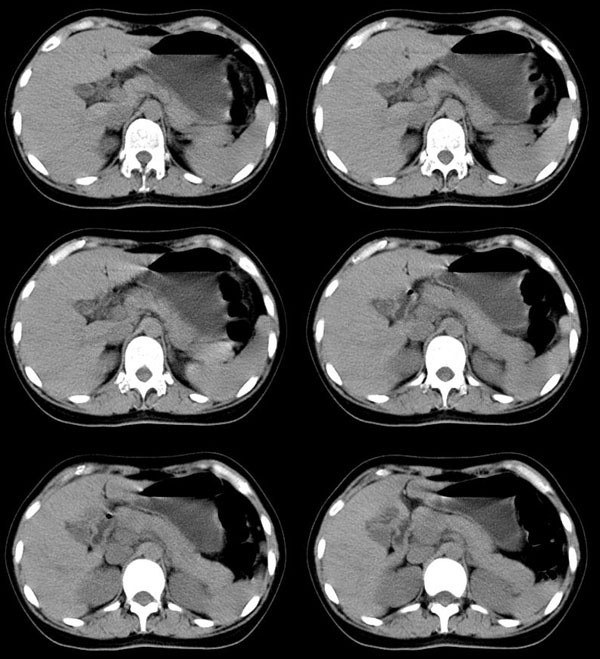

以下是引用guzhongliangddd在2006-11-9 17:55:00的发言:[br]请重点讨论图中箭头所示{脾门部,我首先考虑的是1:血管结构2:胰尾组织??)[br][br][本贴已被 guzhongliangddd 于 2006-11-9 18:01:50 修改过]